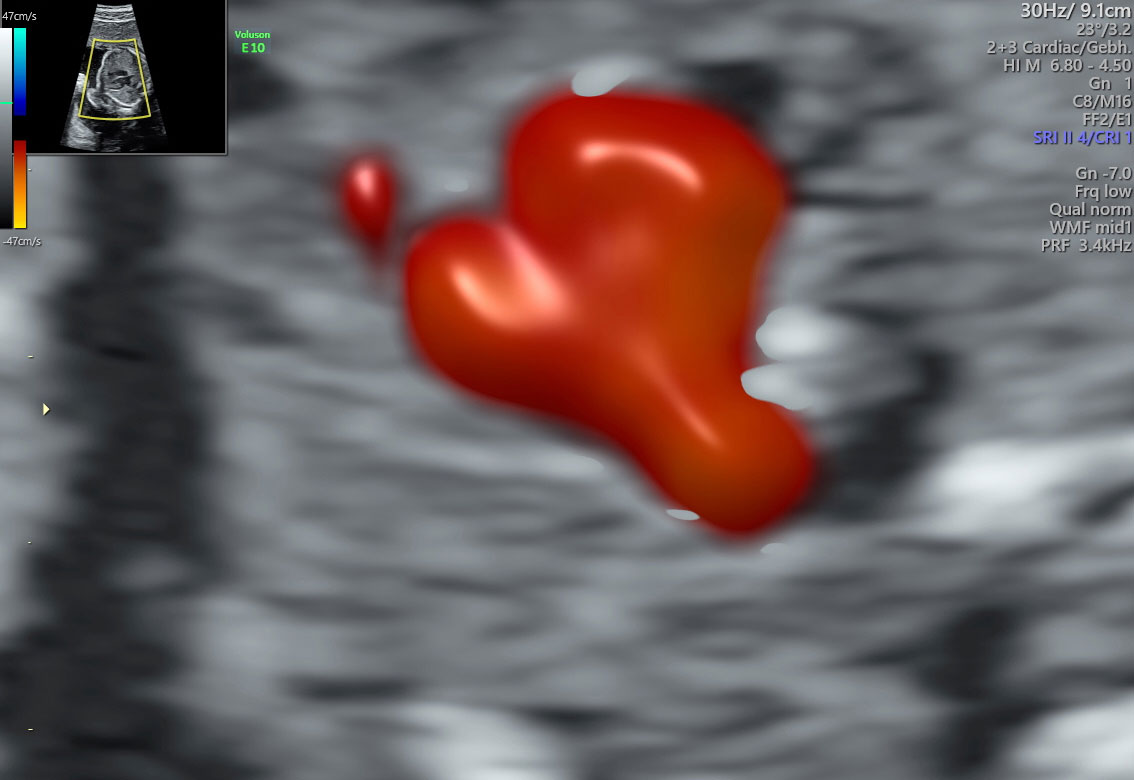

Bilder von Dr. U. Holtkamp

Fetale Herzechokardiographie

Durchgeführt von Dr. Holtkamp

Die sonographische Beurteilung des Herzens kann in Grundzügen auch bereits schon zu Zeiten der Nackentransparenzmessung erfolgen. Auch hier kommt die Matrix-Technologie zum Einsatz, weiterhin eine besondere Farbdopplertechnik, die sich radiance mode nennt.